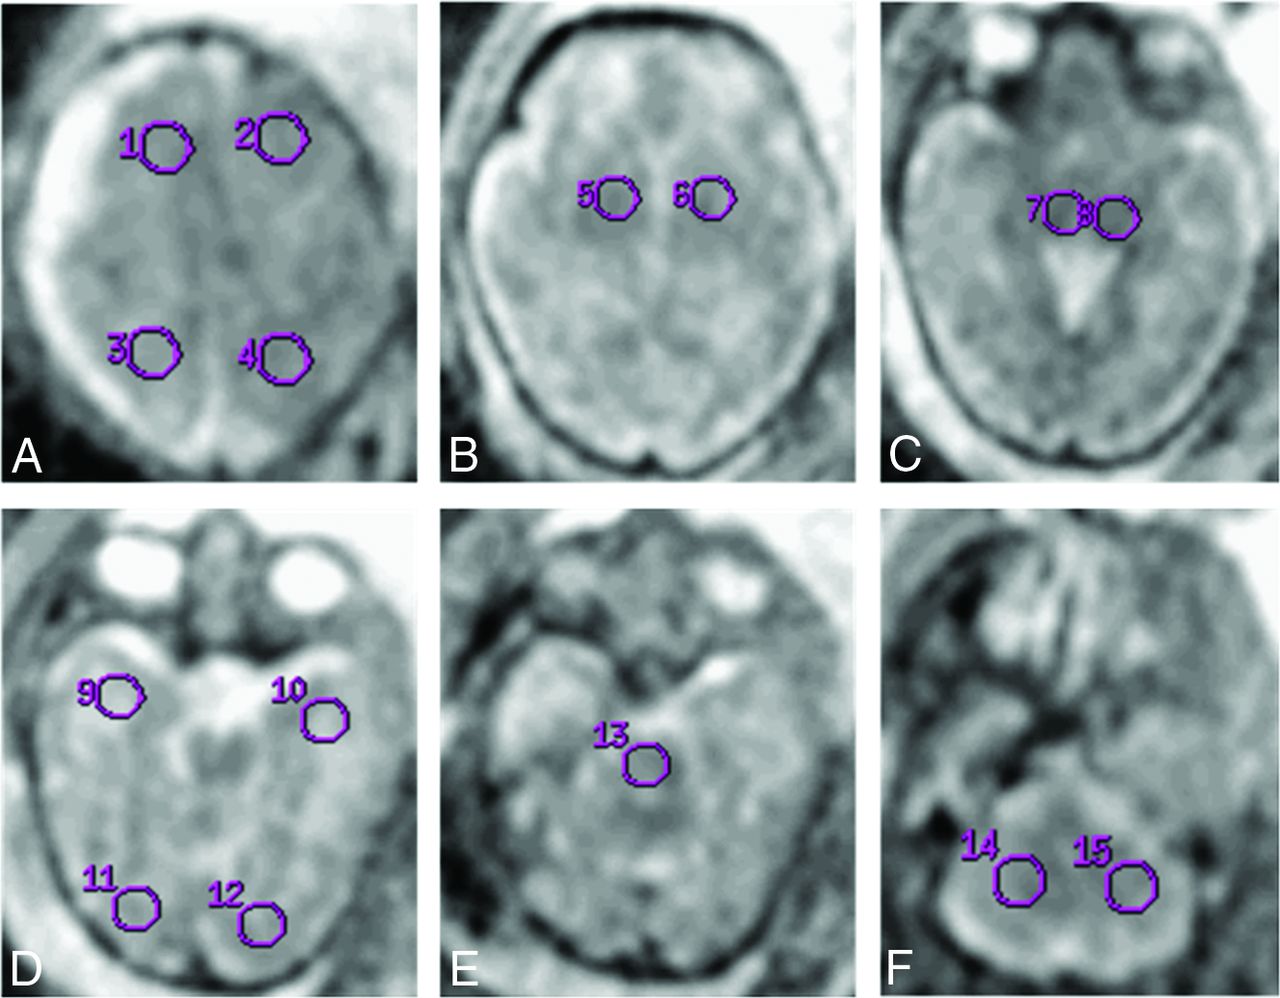

Technical parameters and protocol of the scan are identical to those of our previous published work.25 ROIs were placed as shown in Fig 1. No significant difference between the ADC values of the 2 sides (except for the basal ganglia and the occipital lobe in the CMV group and the temporal lobe in the control group) was shown.

ROI analyzed for apparent diffusion coefficient. ROI placement example. A, 1, 2 = frontal lobe; 3, 4 = parietal lobe. B, 5, 6 = basal ganglia. C, 7, 8 = thalami. D, 9, 10 = temporal lobe; 11, 12 = occipital lobe. E, 13 = pons. F, 14, 15 = cerebellum.